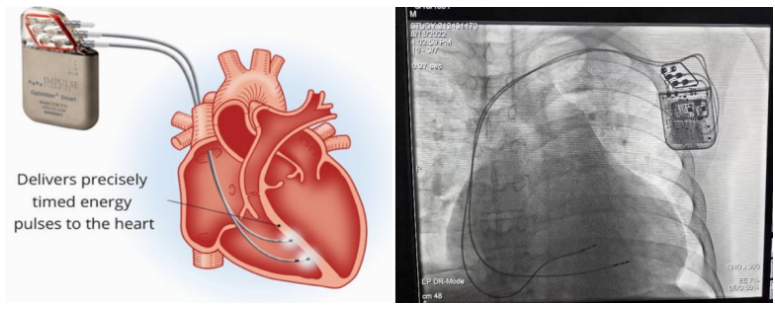

①植入式心臟復(fù)律除顫器

Implantable Cardioverter Defibrillator,ICD

植入式心臟復(fù)律除顫器是一種具有除顫功能的高級起搏器,是一種體積小、能植入患者胸部皮下組織的醫(yī)療設(shè)備。慢性心衰患者易發(fā)生室性心動過速或心室顫動,導(dǎo)致心源性猝死(SCD)。ICD 則能在幾秒內(nèi)自動識別并治療快速室性心律失常,通過低能量心臟轉(zhuǎn)復(fù)和高能量除顫等功能,顯著降低惡性室性心律失常引起的猝死風(fēng)險??杉皶r自動為患者轉(zhuǎn)復(fù)心律,通俗地說就是裝在體內(nèi)的自動除顫儀。

國內(nèi)研發(fā)企業(yè):無雙醫(yī)療、邁瑞、魚躍、久心、微創(chuàng)、維偉思、麥邦等